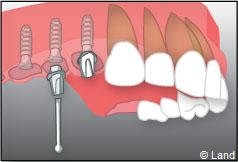

Le chirurgien-dentiste après une anesthésie locale pratique une incision, puis il décolle la gencive pour accéder à l’os alvéolaire.

Ensuite il prépare l’emplacement de l’implant dans l’os en passant plusieurs forets de diamètre croissant. Le forage de l’os se fait à vitesse maîtrisée et lente sous irrigation, pour respecter la structure osseuse et éviter tout échauffement de celle-ci. Le praticien arrête lorsqu’il a obtenu un puits d’un diamètre très légèrement inférieur à l’implant à poser.

L’implant est placé dans l’os le plus souvent par vissage et doit avoir une liaison forte avec l’os. Le praticien replace alors la gencive et pose des points de suture.

Exemple d’un implant unitaire pour remplacer une dent antérieure manquante.